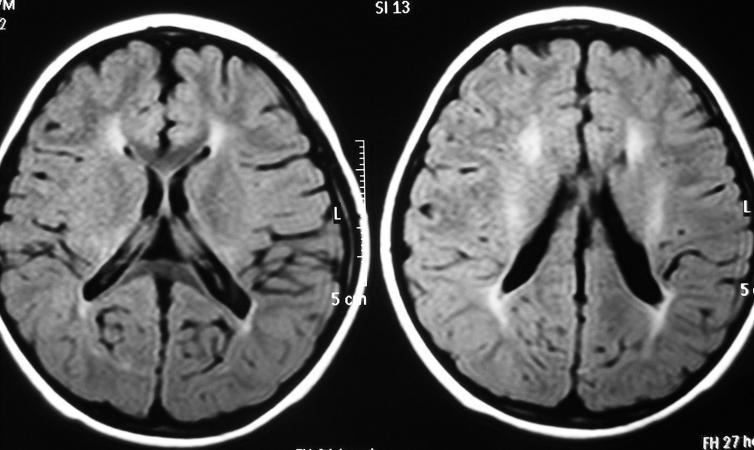

主要与脑缺血缺氧有关,多见于早产儿,是造成脑瘫的主要原因

影像学发生于侧脑室周围,侧脑室扩大,脑白质减少。扩大的侧脑室外缘常不规则为其特点,多为双侧脑室同时扩大。脑白质减少,脑皮层与脑室侧缘相近。MRI T1呈低信号,T2呈高信号。